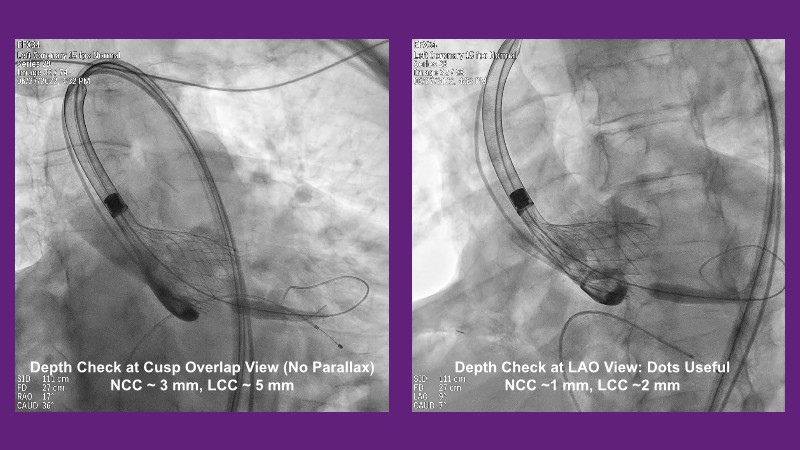

Don’t miss this PCR Tokyo Valves 2025 session replay, where leading experts share key techniques for simplifying and optimising TAVI procedures with the Evolut device. This session covers essential insights into safely performing procedures on patients with various anatomical types using the self-expandable valve, while emphasising the importance of long-term patient care and outcomes. Discover valuable strategies for surgical explantation of transcatheter aortic bioprostheses, coronary cannulation, and commissural alignment post-TAVR. Learn expert tips for streamlining procedures, such as semi-rapid pacing, using Dryseal long, and skipping pre-BAV to improve TAVI results. Watch now to stay ahead in the field!

- To understand simple procedure as semi-rapid pacing, using Dryseal long and skip pre-BAV